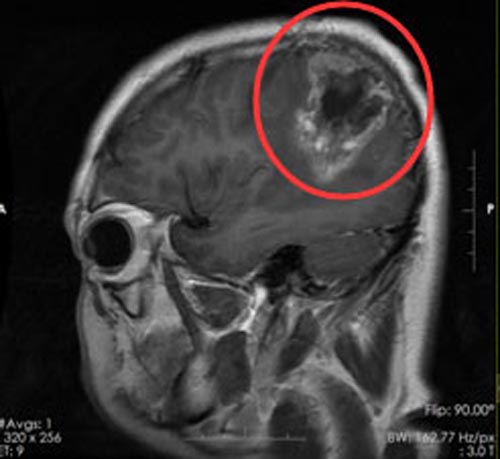

26岁的小肖, 10个月前因右顶枕叶占位在当地医院行肿瘤切除手术,术后病理提示:间变性室管膜瘤WHOⅢ级,手术后予以放疗,出院后病情稳定,无不适症状。几天前回医院复查头颅MR,提示:右顶枕叶占位,小肖和家人都清楚:这是肿瘤复发了。

由鲁明副院长主刀在全麻下行“右顶枕叶复发间变性室管膜瘤切除术”,手术非常顺利,神经功能没有损伤,小肖担心的情况没有发生,他可以自己四处走动,生活质量没有影响。术后病理检查结果:高级别神经上皮肿瘤,考虑为胶质母细胞瘤,WHOⅣ级。

▲手术前